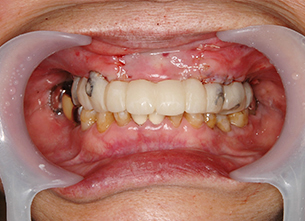

症例1 : 上下顎無菌顎症例

69歳、男性。

• 上顎は両側サイナスリフトと同時に即時荷重を行った。

• 下顎は抜歯即時埋入即時荷重を行った。

• 最終補綴物は、チタンのP.I.B.とM.B.のコンビネーションで修復した。

• 本症例の要旨は第39回日本口腔インプラント学会(大阪)にて症例報告した。